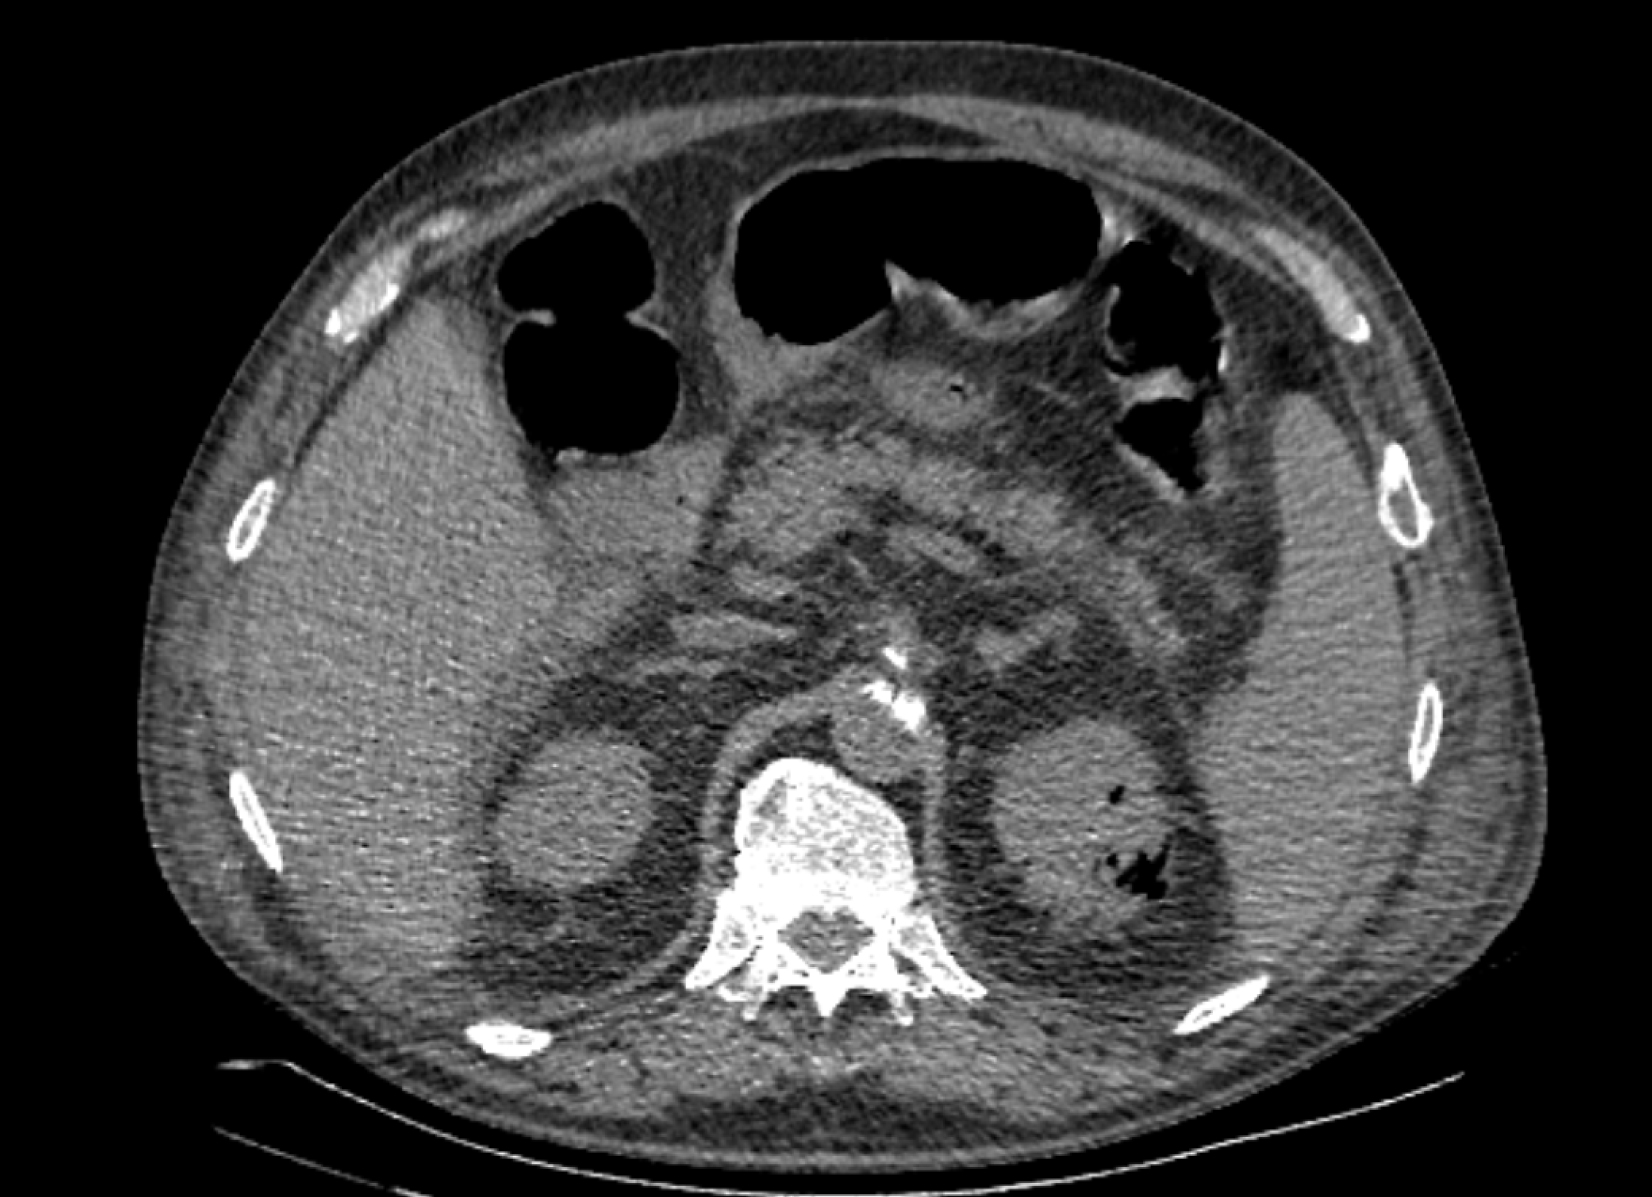

На следующий день состояние пациента оставалось тяжелым, с отрицательной динамикой, креатинин сыворотки возрос до 735,2 ммоль/л, Появились жалобы на слабость, тошноту. При осмотре: живот мягкий, вздут по всем отделам, при пальпации болезненный. Область почек не изменена, при пальпации безболезненна, патологических изменений в области почек не выявлено. Симптом поколачивания отрицательный билатерально. При УЗИ были обнаружены плевральный выпот по 300–400 мл с каждой стороны, гепатомегалия, увеличение размеров селезенки, асцит. Кроме того, в обеих почках были визуализированы тени, характерные для конкрементов. По данным компьютерной томографии (КТ) конкрементов не обнаружено, но в лоханке, на всем протяжении левого мочеточника и, частично, в правом мочеточнике, а также в мочевом пузыре визуализировался газ (рис. 1–6).

Рис. 4. Компьютерная томография органов брюшной полости, забрюшинного пространства, органов малого таза. Газ в почках

Рис. 5. Компьютерная томография органов брюшной полости, забрюшинного пространства, органов малого таза. Газ в левой почке

Рис. 6. Компьютерная томография органов брюшной полости, забрюшинного пространства, органов малого таза. Газ в верхнем полюсе левой почки